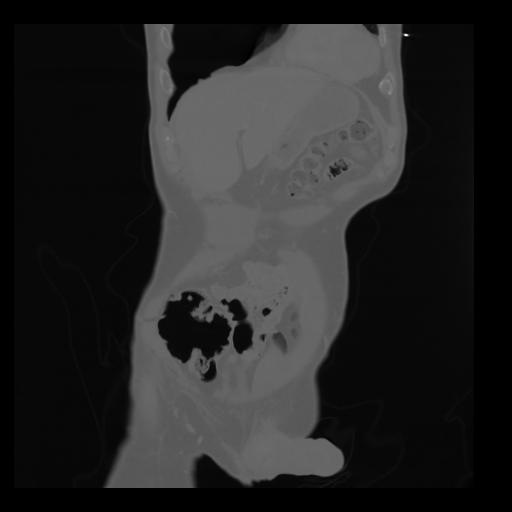

35 CUERPO,CE,Coronal,3.000,CUERPO,Coronal,